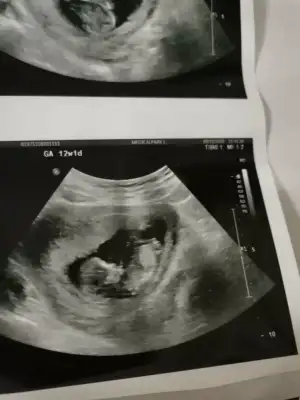

Bende 12 haftalık hamileyim cinsiyetini merak ediyorum banada bakarmısınız

Eklentiler

• IMG_20201211_144150.webp

IMG_20201211_144150.webp

17,3 KB · Görüntüleme: 60

• IMG_20201211_144131.webp

IMG_20201211_144131.webp

14,8 KB · Görüntüleme: 51